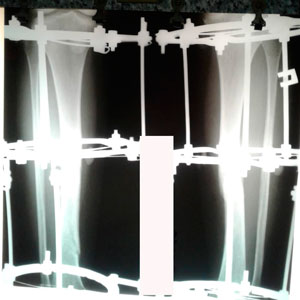

рентген перед снятием аппаратов

IMG_8339-18-01-20-08-10.JPG

IMG_8338-18-01-20-08-10.JPG

Дата снятия аппаратов - 14.01.2020 094f316296.gif